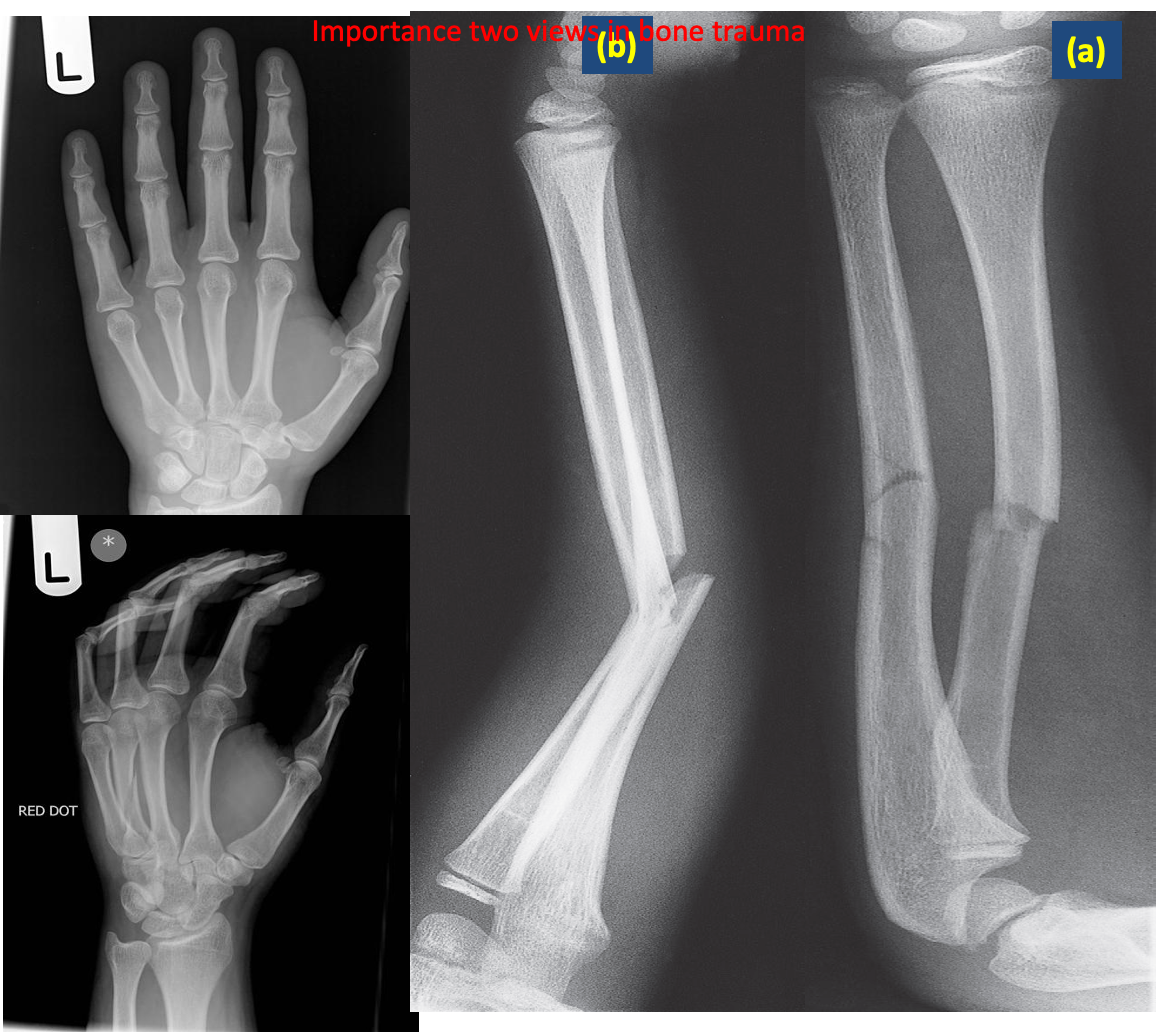

- In bone one view is no view

- The radiologist should obtain at least two (2) views of the bone involved at 90° angles to each other .

Value of two views for demonstrating the position of fractures.

(a) The fractures of the radius and ulna show little displacement on the frontal projection.

(b) The lateral view, however, shows a marked angulation.